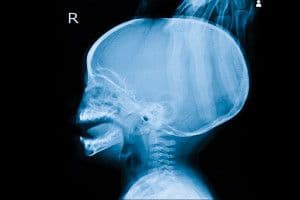

La hidrocefalia se define como el aumento de la cantidad de líquido cefalorraquídeo dentro del cráneo. El líquido cefalorraquídeo (LCR) sirve para proteger el cerebro y la médula espinal, a los que baña por completo. Cuando se encuentra en cantidad excesiva (hidrocefalia), puede ocasionar un aumento de la presión en su interior (“hipertensión intracraneal”), afectando al funcionamiento de los órganos del interior del cráneo (cerebro, cerebelo y vasos sanguíneos).

El diagnóstico parte de una sospecha clínica y una exploración física y neurológica completas. Tiene especial utilidad la exploración del “fondo de ojo” (principalmente en niños mayores). Consiste en ver con un oftalmoscopio, a través de la pupila del niño, el fondo del ojo. Las pruebas de imagen (resonancia magnética craneal, tomografía computarizada, ecografía transfontanelar en los niños más pequeños) confirman el diagnóstico en la mayoría de los casos.